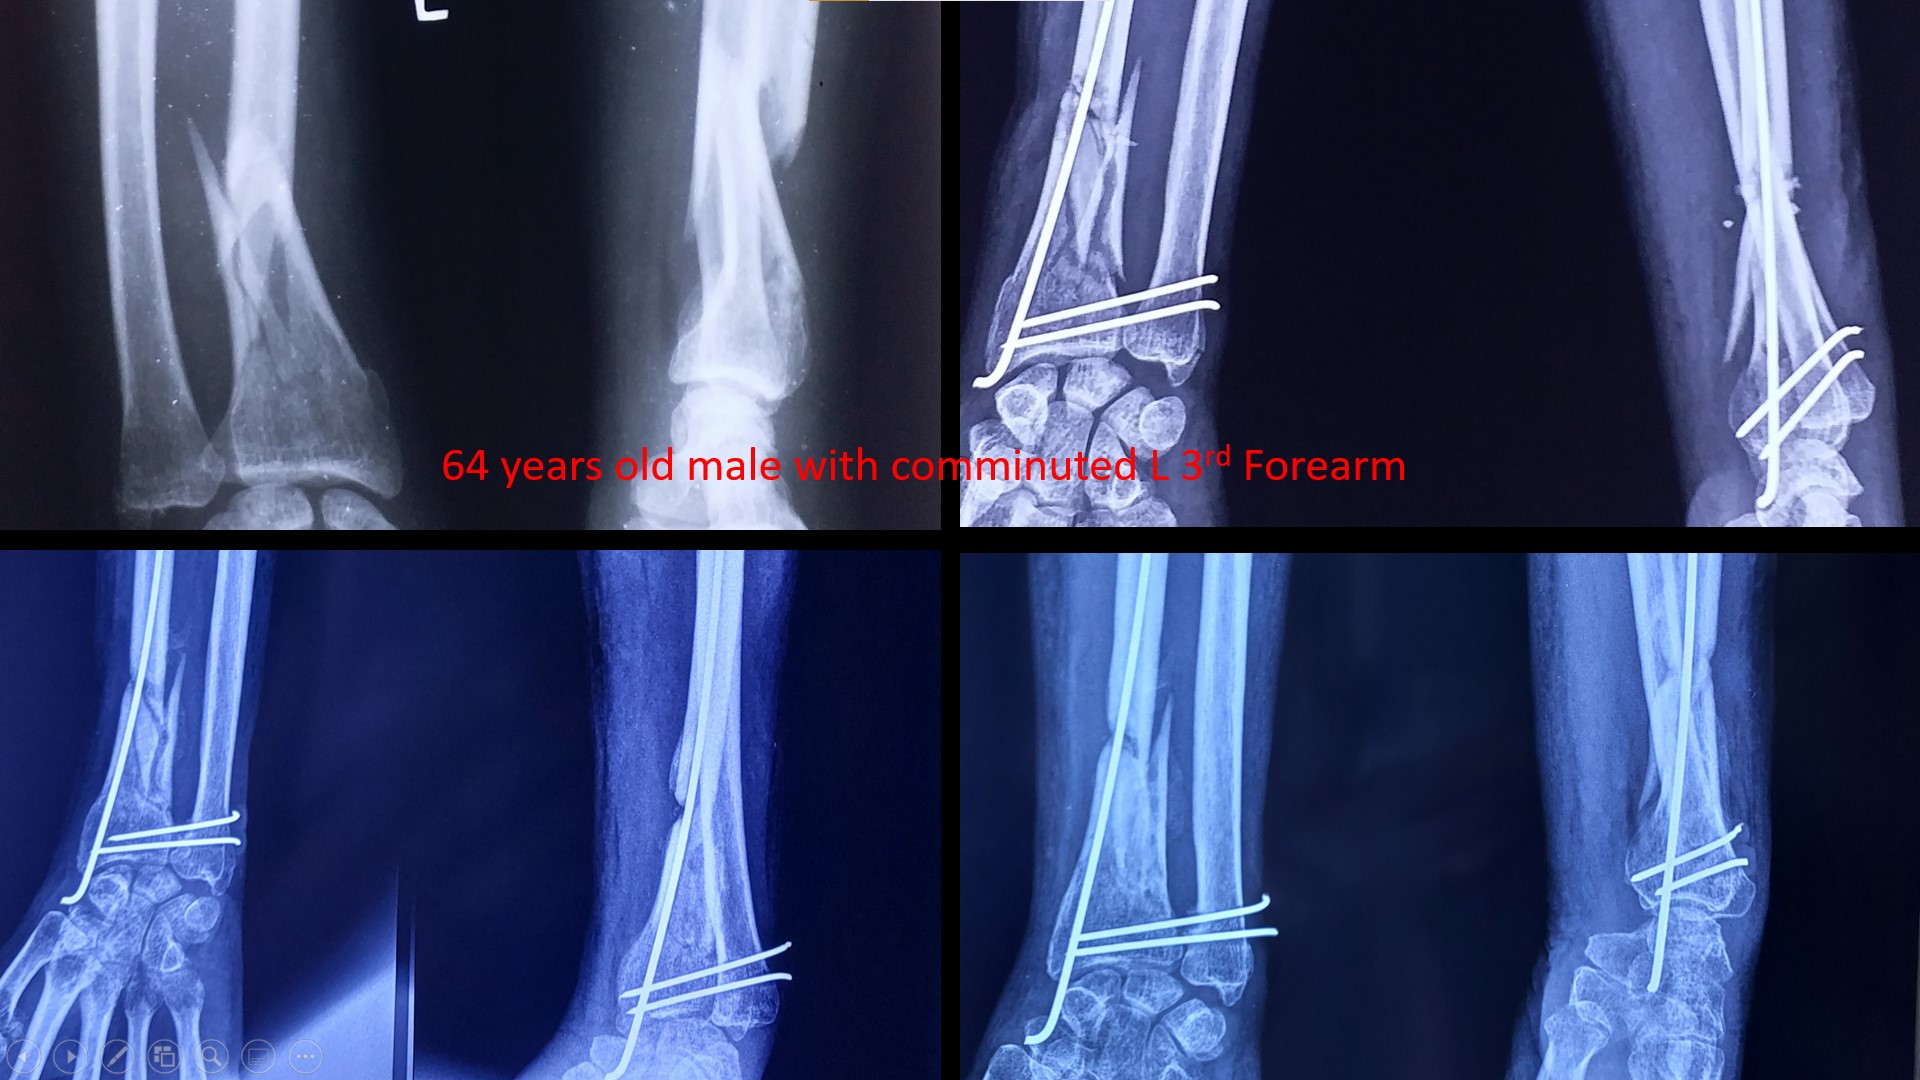

FRACTURE LOWER 3RD FOREARM